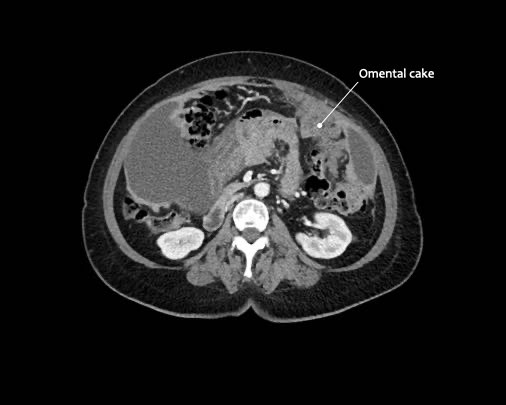

Mạc nối bánh

Mạc nối là một trong những cấu trúc trong ổ bụng đầu tiên bị xâm lấn bởi ung thư phúc mạc.

Hình ảnh gọi là “mạc nối bánh” (omental cake) là kết quả của các nốt khối u lan rộng trong mạc nối lớn.

Tổn thương này có hình ảnh rất điển hình trên cả siêu âm và CT.

Hình ảnh

Hình ảnh CT của mạc nối bánh nổi trong dịch cổ trướng (mũi tên).

Mạc nối nằm ở bụng trái, trải dài từ bờ ngoài dạ dày xuống phía dưới.

Hình ảnh cho thấy cấu trúc dạng nốt không đồng nhất rõ rệt, điển hình của mạc nối bánh.

Các chấm trắng trong mạc nối có thể là các mạch máu.